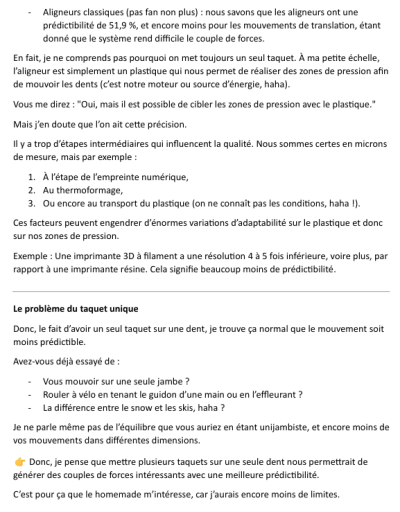

Étape 1 (photo Figure 1)

1. Arc SS ou TMA 7-7 en 18x25, avec une ligature en 8 de 11 à 26, un peu lâche, car je veux profiter des effets parasites sans créer de déviation maxillaire. En général, cela suffit pour cet objectif.

2. Minivis de 1,5 mm de diamètre et 6 mm de longueur (plus proche de la racine de 11)

3. Bras en Blue Elgiloy 18x25, avec double boucle côté intérieur. La partie horizontale doit être 1,15 fois plus grande que l’espace à fermer entre la canine et l’incisive. J’ajoute une gaine en plastique dessus pour éviter de blesser le patient.

4. Ligature en 8, car même si les effets parasites ne m’inquiètent plus face au risque d’AI, au pire, je risque peu de proversion coronaire → pseudo-ingression → accentuation de l’infra. Je temporise ces effets au maxx avec la ligature et les corrigerai par la suite a l’etape 2 avec les effets parasites contraires (Les mouvements de va-et-vient sont déconseillés, mais ici, ils seront négligeables.)